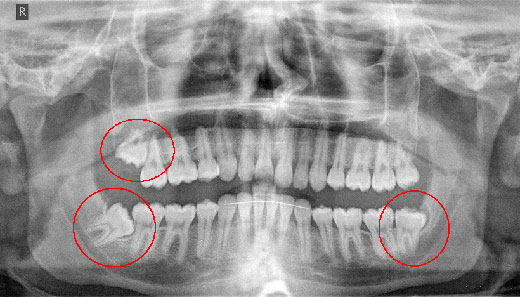

Τέλος οι γνωστοί σε όλους μας φρονιμίτες που δημιουργούν πολλά και έντονα προβλήματα, κυρίως σε νεαρή ηλικία και όχι μόνο.

Μία συχνή επέμβαση που πολλοί τη θεωρούν σχετικά απλή, αλλά στην πραγματικότητα πολλές φορές δεν είναι έτσι.

Σημαντικό είναι επίσης, κυρίως σε νέους η μεταμόσχευση δοντιών, όπου ανάλογα με την διάπλαση των ακροριζίων η επιτυχία της μεταμόσχευσης φθάνει σε μεγάλο ποσοστό. Έτσι το κενό που δημιουργείται μετά από απώλεια ενός μόνο γομφίου, μπορεί με μεγάλη πιθανότητα να κλείσει με μεταμόσχευση ενός φρονιμίτη στη θέση αυτή.